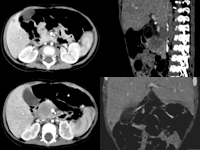

患儿,女,6个月,主因巩膜、皮肤、尿色黄,粪便色白20余天入院。在我院行腹部CT检查,显示胰头有类圆形软组织密度包块影,形态欠规则,无明显强化。肝大,肝内可见多个大小不等圆形低密度影,无强化,肠系膜上动静脉受推移。 CT诊断:胰头占位(胰母细胞瘤可能性大),肝内转移。

图1、2 CT增强横轴位及矢状位二维重建:胰头类圆形软组织密度占位,未见明显强化(箭头所示)

图3、4 CT增强轴位及冠状位二维重建显示:肝内结节状低密度灶,未见强化(箭头所示), http://www.100md.com